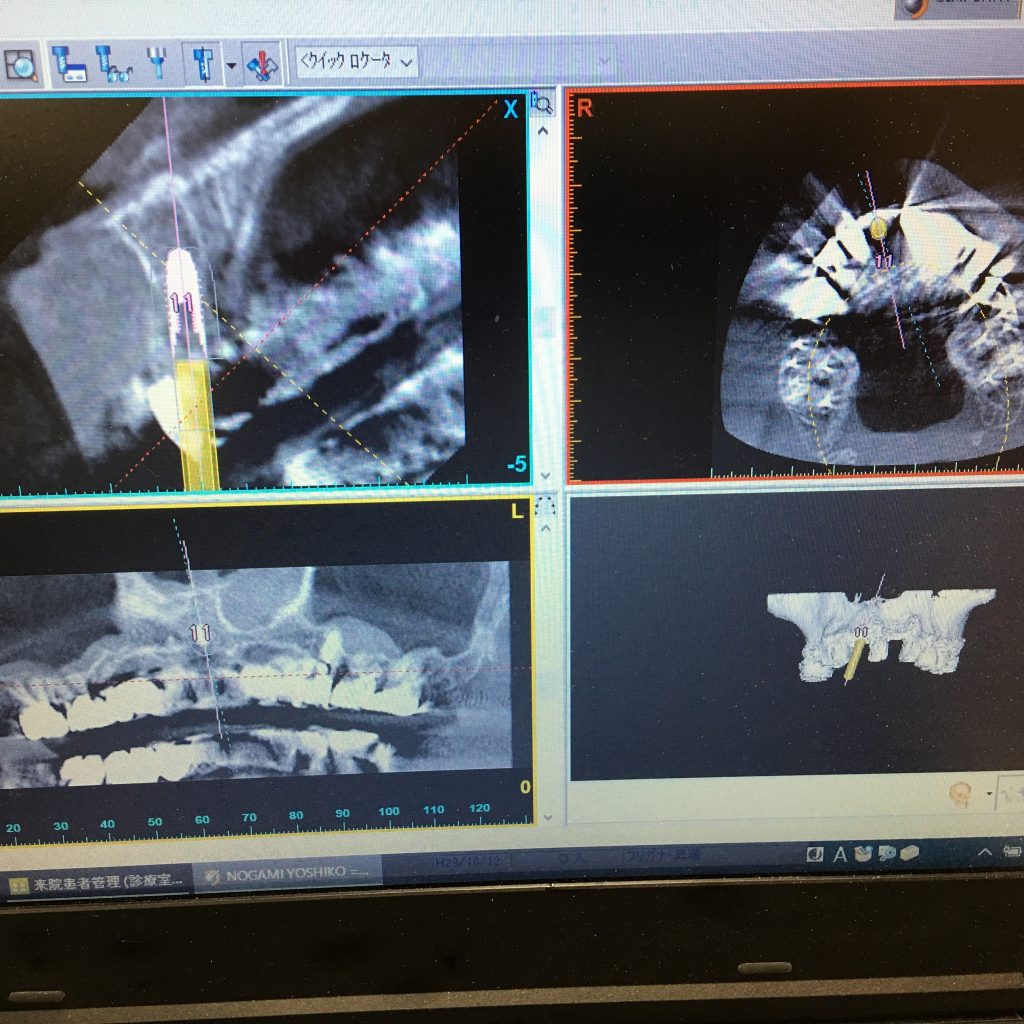

インプラントのプランニング会社シムプラント